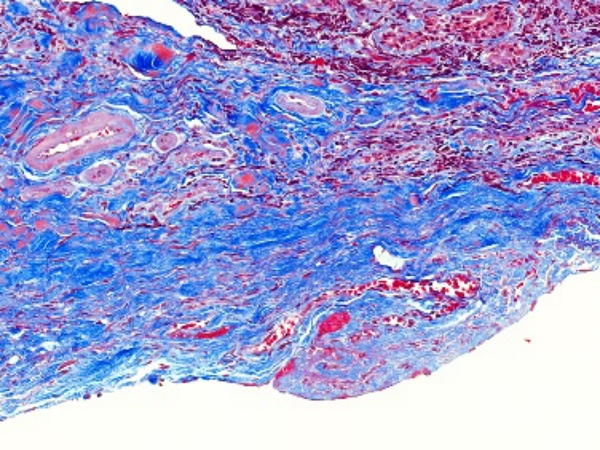

免疫组化(Immunohistochemistry,IHC)是一种利用抗原 - 抗体特异性反应来定位和定性组织细胞中特定抗原的技术,在病理学、肿瘤学等众多领域发挥着关键作用。**一、原理**1. 抗原 - 抗体反应 - 基于抗原与抗体之间的高度特异性结合。组织细胞中的蛋白质、多肽等抗原成分能够被相应的特异性抗体识别并结合

400-9929-003 立即咨询免疫组化(Immunohistochemistry,IHC)是一种利用抗原 - 抗体特异性反应来定位和定性组织细胞中特定抗原的技术,在病理学、肿瘤学等众多领域发挥着关键作用。

特殊染色是病理学和组织学中使用的一种染色方法,用于显示组织或细胞中的特定成分,这些成分在常规的苏木精 - 伊红(HE)染色中可能无法清晰地显示。以下是关于特殊染···...